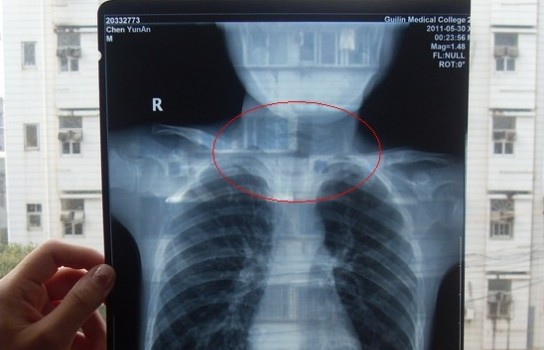

胸部正位X光片圖

2011年5月29日下午,陳先生的兒子安安出現(xiàn)嘔吐、肚子疼痛等癥狀。陳先生立即將兒子送往醫(yī)學(xué)院附院,根據(jù)醫(yī)生開(kāi)出的會(huì)診單,分別對(duì)安安做了腹部立臥位2次和胸部正位1次共3次X光片檢查、診斷。醫(yī)生看X光片后排除了腸梗阻病因,判斷是闌尾炎。經(jīng)過(guò)治療,不久安安身體痊愈。

可是,陳先生的一次偶然發(fā)現(xiàn),讓他們一家過(guò)上了提心吊膽的日子。因?yàn)椋诎舶渤鲈阂粋€(gè)月后,陳先生偶然翻出孩子治療期間的X光片。發(fā)現(xiàn)在X光片中,孩子的生殖器官以及甲狀腺等敏感部位也在被放射區(qū)域中。而陳先生上網(wǎng)查到:人體拍攝X光片是有一定輻射的,并且輻射有可能引起基因變異等問(wèn)題,他立馬陷入恐慌中。

至于,為什么拍攝X光時(shí),孩子的敏感部位也在放射區(qū)域內(nèi),這讓陳先生百思不得其解。為此,他專門(mén)到醫(yī)學(xué)院進(jìn)行了質(zhì)疑。而醫(yī)院的醫(yī)務(wù)人員說(shuō),拍腹部X光片就要照到睪丸,要檢查睪丸是否正常,而且怕小孩亂動(dòng),所以要照寬些。